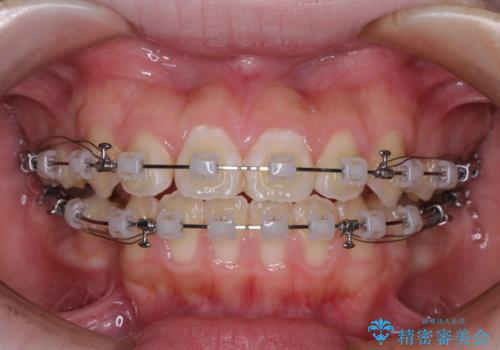

- クリアブラケット

舌の突出癖により上下前歯は接触できず、更には前方に押し出されて出っ歯になっている状態でした。

上下左右の第一小臼歯4本を抜歯し、ワイヤー装置での抜歯矯正を行っていくのですが、原因である舌の突出癖を改善しないことには治療がうまく進められないため、舌のトレーニングを徹底するよう指導していくこととしました。

当初は舌のトレーニングがうまくできていなかったのですが、途中から奏効し、非常に短い期間で治療を終えることができました。